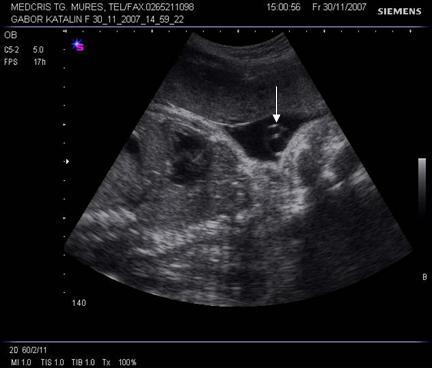

Planul III sau planul frontooccipital, pentru masurarea diametrelor biparietal si frontoocipital. Ecoul de mijloc frontoocipital este intrerupt in zona cavum septum pellucidi, anecogena, situata anterior de ventriculul III. Acesta este situat intre doi nuclei talamici hipoecogeni si apare ca o despicatura mica sau o linie.

Fig. nr. 151 Planul III de sectiune transversala a craniului fetal.